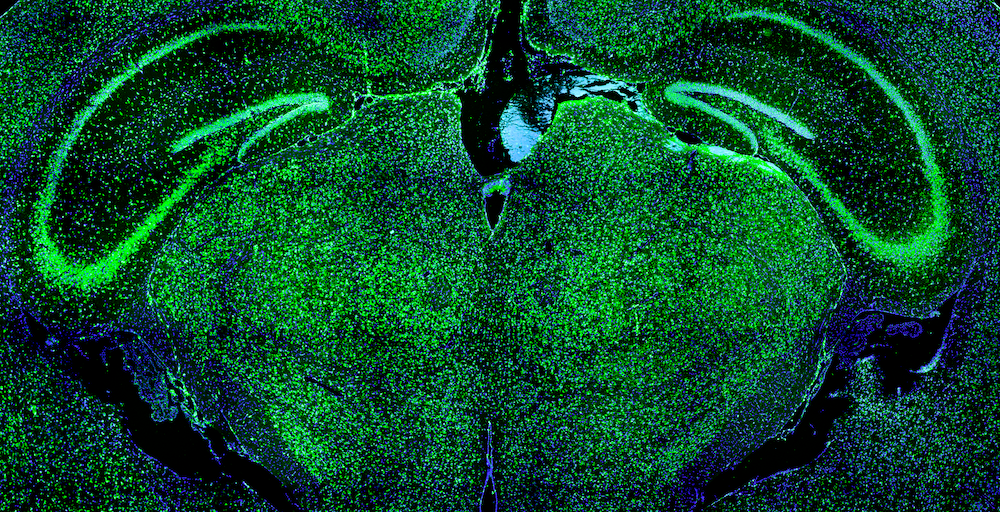

UMass Chan scientists receive $2.3 million from Rett Syndrome Research Trust for research

Erik Sontheimer, PhD, the Pillar Chair in Biomedical Research and professor of RNA therapeutics; Jonathan Watts, PhD, professor of RNA therapeutics; and Scot Wolfe, PhD, professor of molecular, cell & cancer biology, were awarded $2.3 million in new funding from the Rett Syndrome Research Trust to utilize base-editing and prime-editing technologies to correct mutations in MECP2.

Current treatments for Rett syndrome symptoms are palliative, but gene therapy clinical trials aimed at addressing the disease’s underlying causes are underway.

“I am cautiously optimistic there’s a good chance that these gene therapy approaches are going to be successful at making some difference. The editing approaches we’re working on have the chance to change disease outcomes even more profoundly, and perhaps enable patients to get much closer to normalcy, especially if the disease can be caught earlier,” Dr. Watts said.